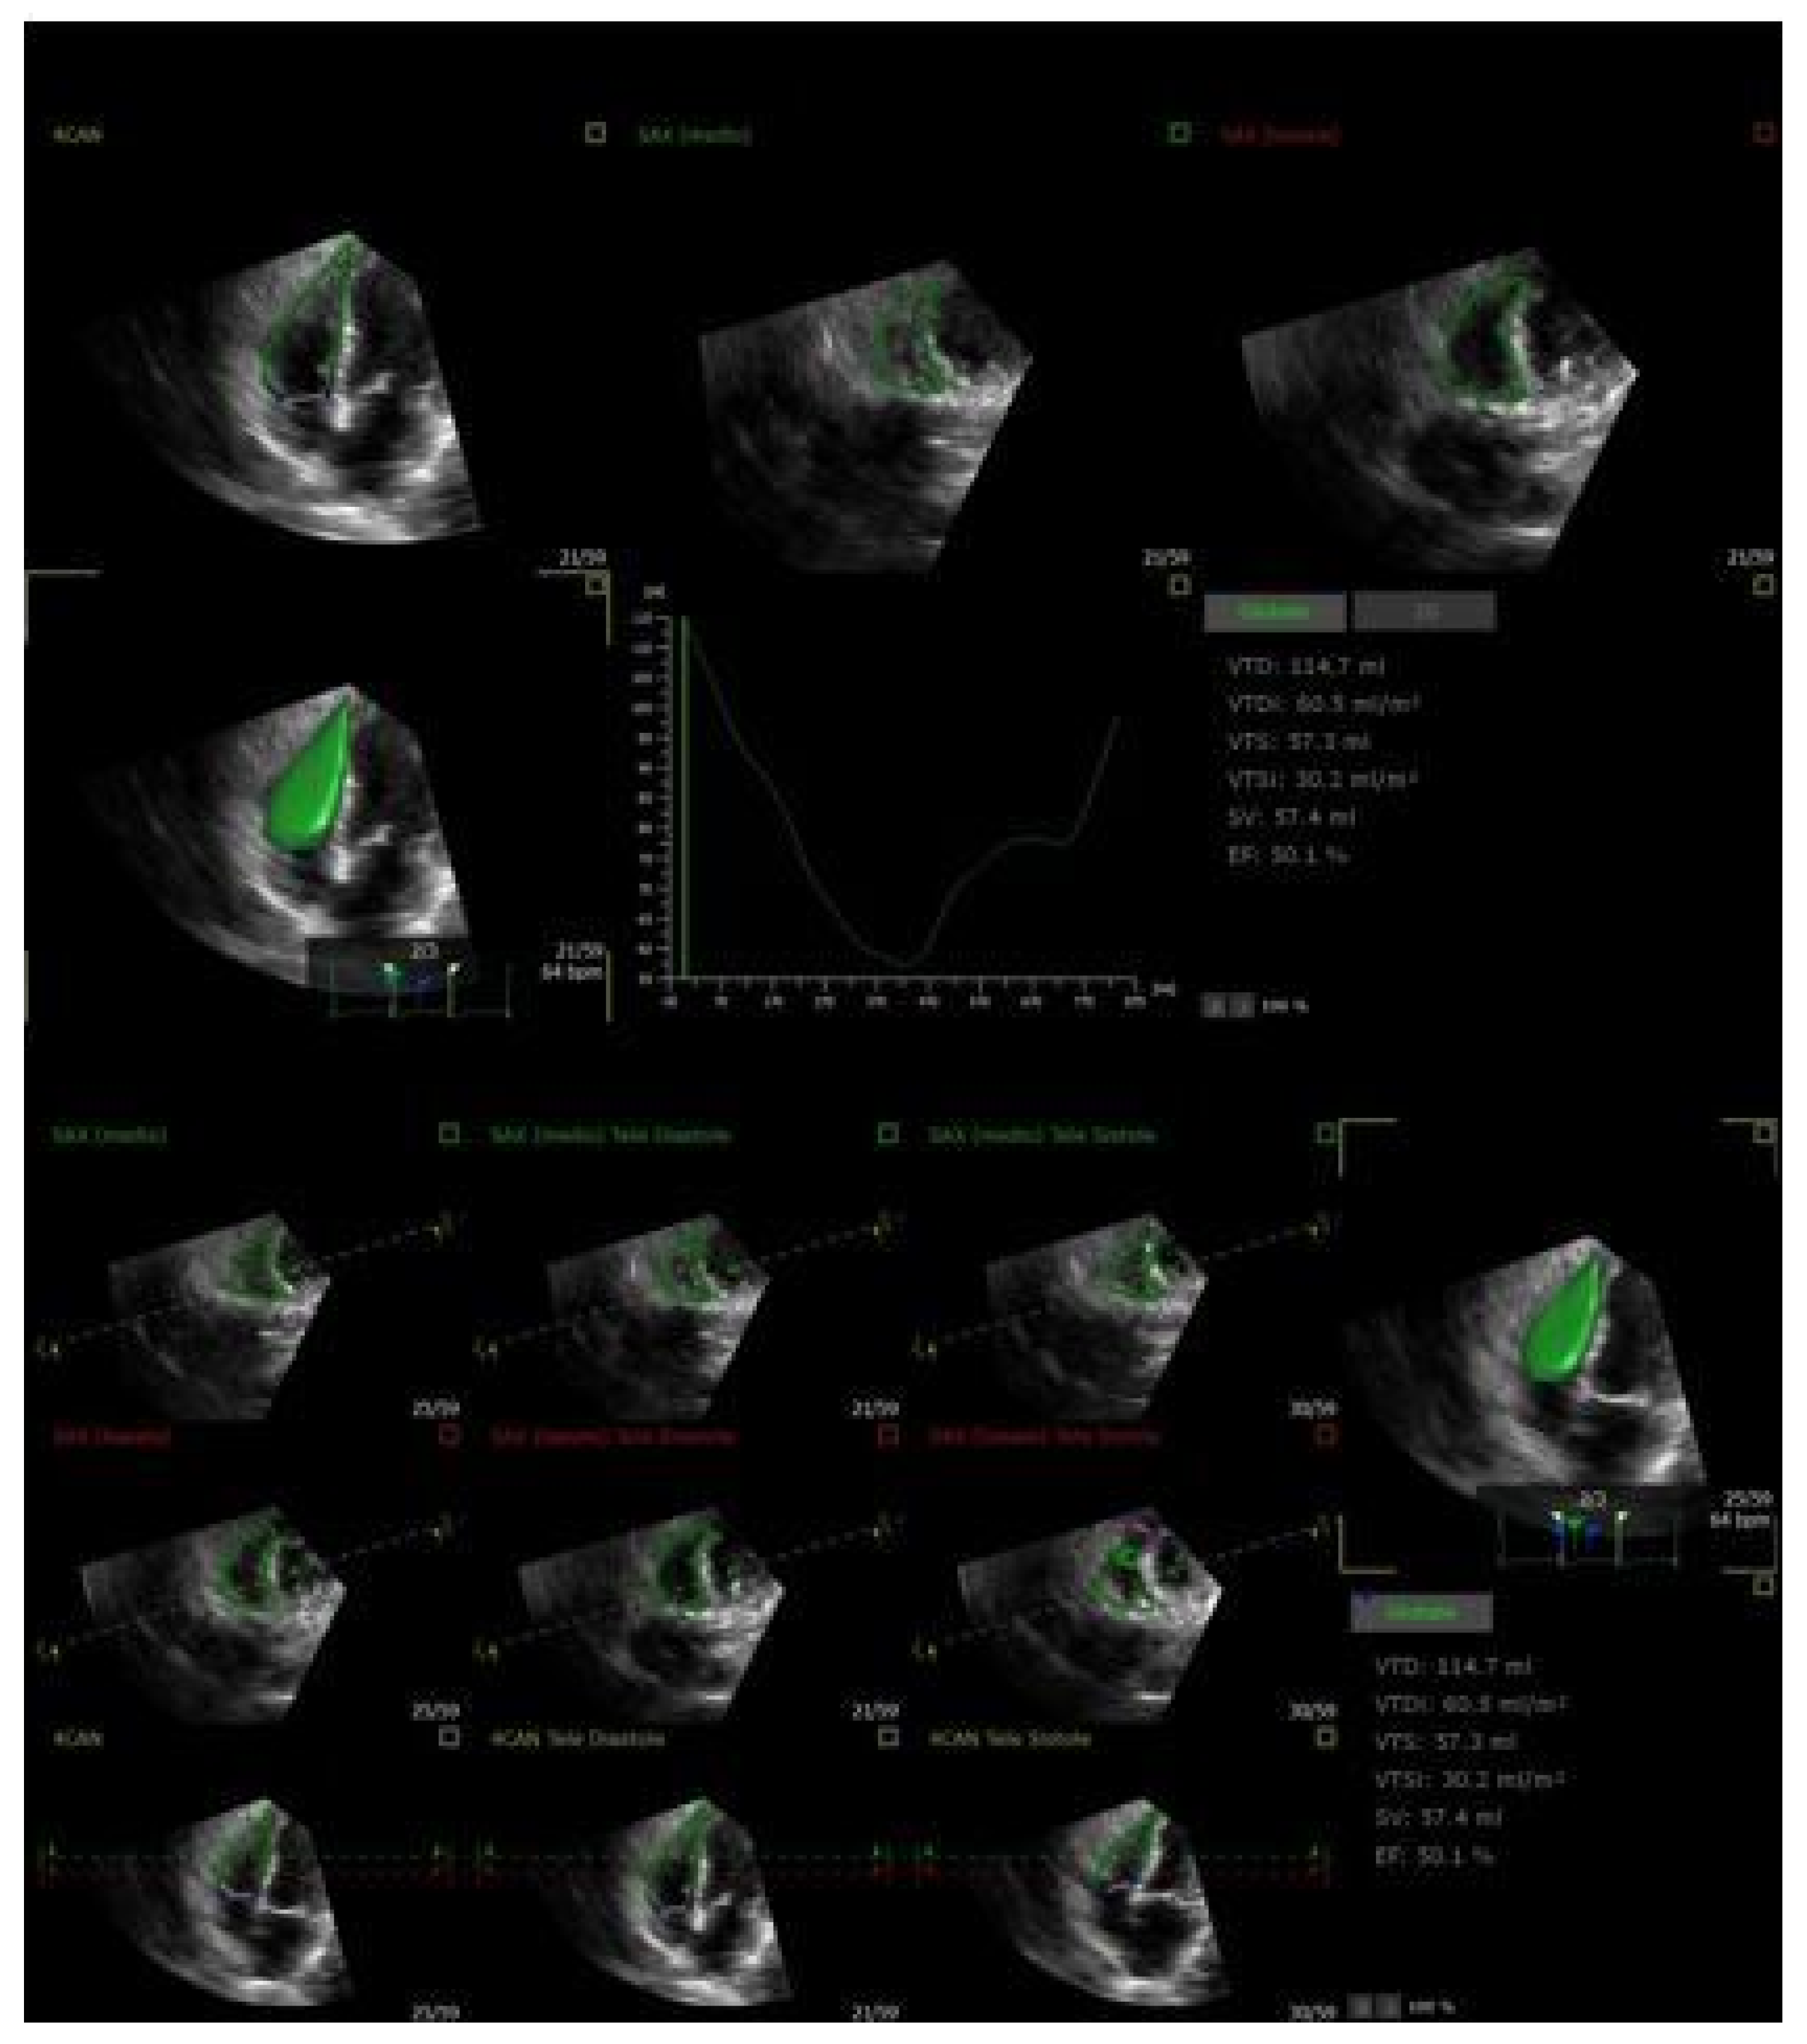

| 3D Echocardiography | RV ejection fraction (RVEF), RV volumes | Volumetric, less geometrically biased | Requires good acoustic window, technically demanding, poorly characterized prognostic impact in the context of TTVIs |